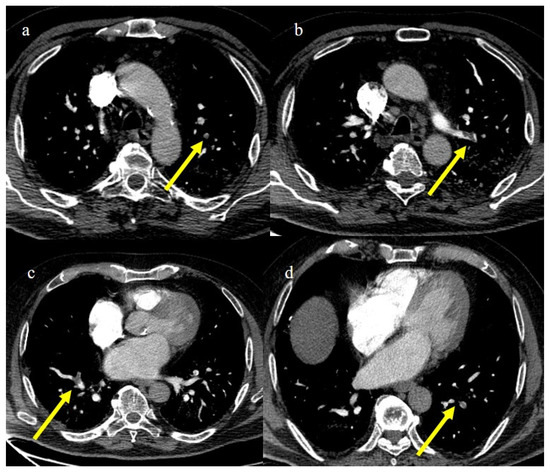

4.1. Small Bowel Ischemia and Ischemic Colitis

4.2. Splenic and Renal Infarction

- Bonaffini, P.A.; Franco, P.N.; Bonanomi, A.; Giaccherini, C.; Valle, C.; Marra, P.; Norsa, L.; Marchetti, M.; Falanga, A.; Sironi, S. Ischemic and hemorrhagic abdominal complications in COVID-19 patients: Experience from the first Italian wave. Eur. J. Med. Res. 2022, 27, 1–9. [Google Scholar] [CrossRef]

- Peshevska-Sekulovska, M.; Boeva, I.; Sekulovski, M.; Zashev, M.; Peruhova, M. Gastrointestinal Ischemia—Stumbling Stone in COVID-19 Patients. Gastroenterol. Insights 2022, 13, 206–217. [Google Scholar] [CrossRef]

- Norsa, L.; Bonaffini, P.A.; Caldato, M.; Bonifacio, C.; Sonzogni, A.; Indriolo, A.; Valle, C.; Furfaro, F.; Bonanomi, A.; Franco, P.N.; et al. Intestinal ischemic manifestations of SARS-CoV-2: Results from the ABDOCOVID multicentre study. World J. Gastroenterol. 2021, 27, 5448–5459. [Google Scholar] [CrossRef]

- Singh, B.; Kaur, P. COVID-19 and acute mesenteric ischemia: A review of literature. Hematol. Transfus. Cell Ther. 2020, 43, 112–116. [Google Scholar] [CrossRef]

- Fathy, A.; Rizk, A.; Elnekeidy, A.; Gharraf, H.S.; Abdelgawad, M.S.; Samir, A. Imaging of COVID-19 vasculopathy from head to toe: Egyptian collective experience after 2 years of the pandemic. Egypt. J. Radiol. Nucl. Med. 2022, 53, 1–21. [Google Scholar] [CrossRef]

- Caruso, D.; Zerunian, M.; Pucciarelli, F.; Lucertini, E.; Bracci, B.; Polidori, T.; Guido, G.; Polici, M.; Rucci, C.; Iannicelli, E.; et al. Imaging of abdominal of abdominal complications of COVID-19 infection. BJR Open 2021, 2, 20200052. [Google Scholar] [CrossRef]

- Ojha, V.; Mani, A.; Mukherjee, A.; Kumar, S.; Jagia, P. Mesenteric ischemia in patients with COVID-19: An updated systematic review of abdominal CT findings in 75 patients. Abdom. Imaging 2021, 47, 1565–1602. [Google Scholar] [CrossRef]

- Boraschi, P.; Giugliano, L.; Mercogliano, G.; Donati, F.; Romano, S.; Neri, E. Abdominal and gastrointestinal manifestations in COVID-19 patients: Is imaging useful? World J. Gastroenterol. 2021, 27, 4143–4159. [Google Scholar] [CrossRef]

- Keshavarz, P.; Rafiee, F.; Kavandi, H.; Goudarzi, S.; Heidari, F.; Gholamrezanezhad, A. Ischemic gastrointestinal complications of COVID-19: A systematic review on imaging presentation. Clin. Imaging 2020, 73, 86–95. [Google Scholar] [CrossRef] [PubMed]

- Gupta, A.; Sharma, O.; Srikanth, K.; Mishra, R.; Tandon, A.; Rajput, D. Review of Mesenteric Ischemia in COVID-19 Patients. Indian J. Surg. 2022, 85, 313–321. [Google Scholar] [CrossRef]